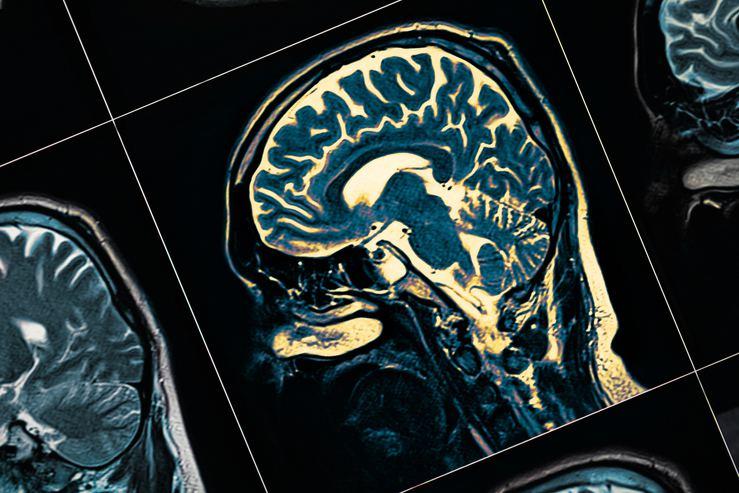

- Günümüzde baş döndürücü bir hızla artan bilimsel gelişmeler sayesinde tıp biliminde de müthiş yenilikler oldu. Bu yenilikler sayesinde ortalama yaşam süresi gelişmiş ülkelerde 80-90 yıla kadar ulaştı. Artmış olan ortalama yaşam süresi sonucunda, yaşlı grubun hastalıklarının da sıklığı arttı.

- Eskiden çoğumuzun hiç duymadığı Alzheimer hastalığı, Parkinson hastalığı, beyin damar hastalıkları gibi hastalıklar artık magazin basınında bile en sık konuşulan konulardan oldu. Bu hastalıkların bu denli artışında, yaşam süresinin artmasının yanı sıra modern yaşamın getirdiği birtakım olumsuzluklar da göz ardı edilemez.